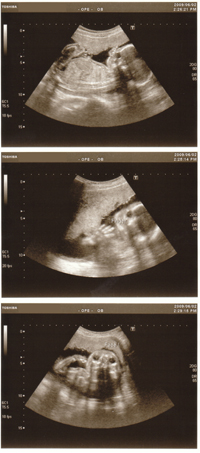

エコー20週

今回のエコーで性別教えてもらいました

結果、、ほぼ 女の子 でしょうとのこと。